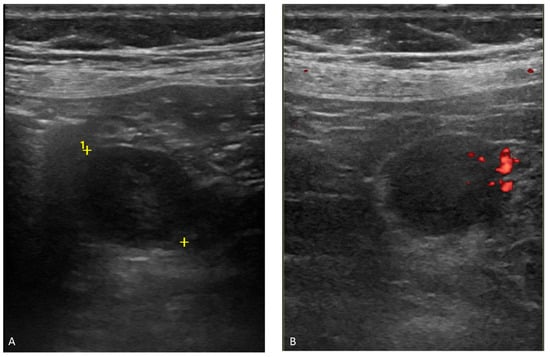

2.3. Endoscopic Ultrasound (EUS)